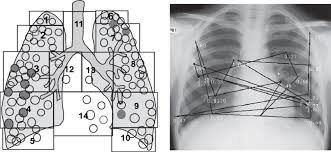

There is no difference between the black and white x's. The throat is responsible for performing a large number of functions, namely the swallowing, speaking and breathing. Most hernias don't need treatment, but some people eventually need. It can be difficult to identify whether chest pain is a sign of a heart attack. Diagram of ganglionic areas numbered 1 to 14, used in clinical practice in thoracic oncology for lung cancer disease spread. Angina pectoris, or stable angina, is chest pain resulting from coronary heart disease. Anatomy of the chest and shoulder, anatomy of the chest organs, anatomy of the chest wall, anatomy of the chest wall and pleura, anatomy of upper chest area, human anatomy, anatomy of the chest and shoulder, anatomy of the chest organs, anatomy of the chest wall, anatomy of. When your gallbladder gets inflamed and swollen, symptoms include pain in your belly, including the area just above your stomach. It starts from the pharynx and extends to the upper end of the esophagus. There are many causes of chest pain.a serious form of chest pain is angina, which is a symptom of heart disease and results from inadequate oxygen supply to the heart muscle. The ribs and sternum make up what is called the 'ribcage.'. It also has branching energy pathways all over the chest. The epidermis is the outermost layer that provides a protective, waterproof seal over the body.

The anatomy of the human ribs (costae) are one of the integral parts of the chest wall; The epidermis is the outermost layer that provides a protective, waterproof seal over the body. Chest pain is a symptom, and so is stomach or esophagus pain, bloating, belching, and a sour taste in back of your throat. Your pectoralis major and pectoralis minor muscles make up most of the muscle mass in your chest. Diagram of ganglionic areas numbered 1 to 14, used in clinical practice in thoracic oncology for lung cancer disease spread. It also protects several vital organs of the chest, such as the heart, aorta, vena cava, and thymus gland that are located just deep to the sternum. The sternum, or breastbone, is a flat bone at the front center of the chest. While it is only around one half of an inch (1 cm) in diameter, the spinal cord both carries nervous signals and processes many reflexes to support the structures of the body.

It lies between the right and left lungs, in the middle of the chest and slightly towards the left of the breastbone. You also may feel an ache in your back or right shoulder blade. This is one of the internal rotator muscles that attach the humerus and internally rotate the arm. Angina pectoris occurs when there is not enough blood getting to the heart due to the narrowing or blockage. Anatomy of the chest and shoulder, anatomy of the chest organs, anatomy of the chest wall, anatomy of the chest wall and pleura, anatomy of upper chest area, human anatomy, anatomy of the chest and shoulder, anatomy of the chest organs, anatomy of the chest wall, anatomy of. Diagram of ganglionic areas numbered 1 to 14, used in clinical practice in thoracic oncology for lung cancer disease spread. The ribs and sternum make up what is called the 'ribcage.'. The throat is responsible for performing a large number of functions, namely the swallowing, speaking and breathing. Angina can be caused by coronary artery disease or spasm of the coronary arteries. The red shaded area is the referred pain caused by the trigger point and the darker red means more people experienced pain in that area. The pectoralis major originates along the clavicle, down the sternum, and across the ribs and inserts into the humerus. Chest pain or discomfort that is new, worsening, or occurs at rest. Your pectoralis major and pectoralis minor muscles make up most of the muscle mass in your chest.